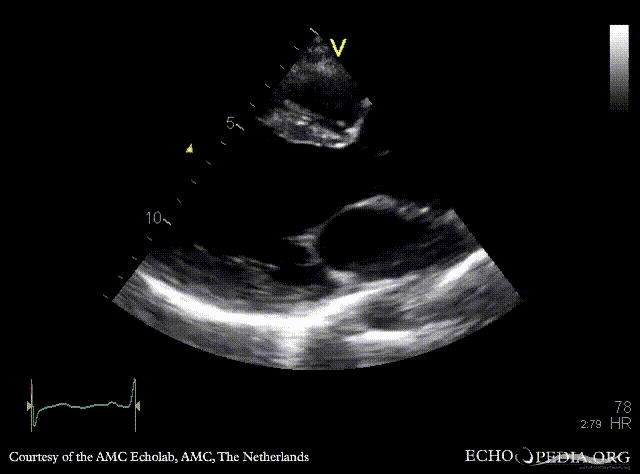

E00444.gif E00445.gif

PLAX: Color Doppler, severe aortic regurgitation A4CH: dilated left ventricle